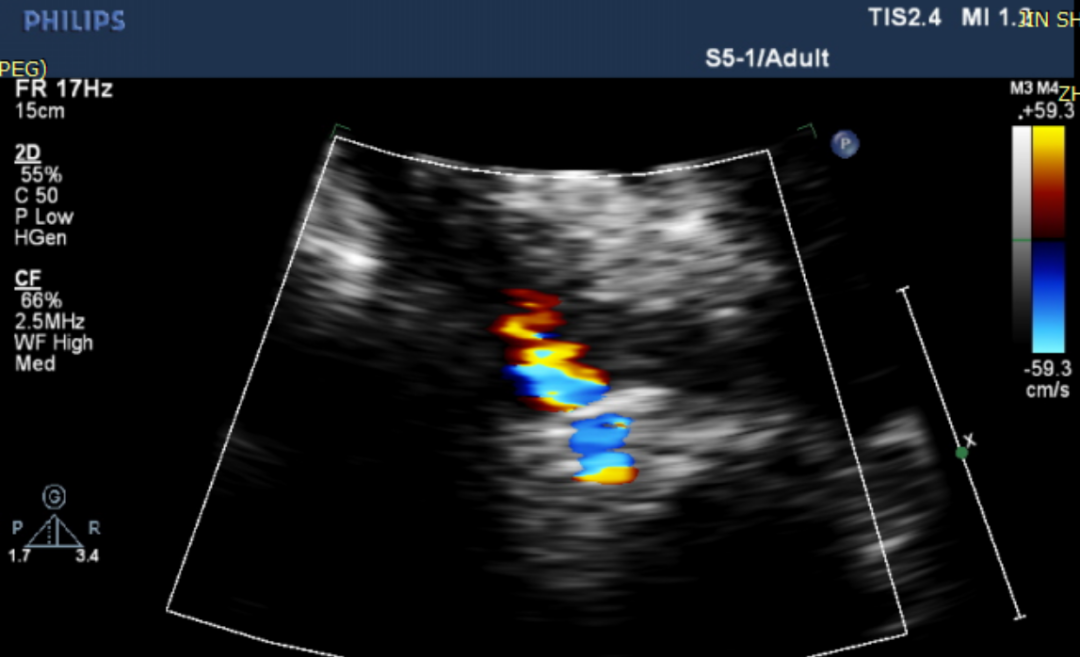

当日接受FreeFlow®经皮房间隔分流系统治疗的患者是一名高龄患者反复胸闷气促13年病症加重半年。术前右心导管显示患者术前平均肺毛细血管楔压15mmHg肺动脉压21mmHg左房压17mmHg右房压5mmHg心排出量3.2。术前患者心动超声数据显示左室射血分数29%、左室直径71mm、二尖瓣重度反流。手术经股静脉穿刺通过输送系统将FreeFlow®经皮房间隔分流器植入房间隔位置形成稳定可控的左向右分流后将输送系统撤出体外。术后即刻测量患者左向右心房分流指数1.4术后患者右心导管显示患者术后平均肺毛细血管楔压11mmHg肺动脉压14mmHg左房压10mmHg右房压3mmHg心排出量3.8。术后心动超声数据显示左室射血分数29%、左室直径67mm、二尖瓣中度反流。综上,患者在植入FreeFlow®经皮房间隔分流系统后,左右心压力负荷减少、肺动脉压下降、心排出量提高、二尖瓣反流减少。